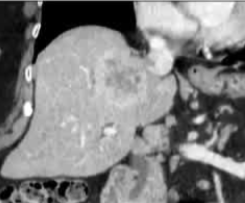

· 单中心、样本量小; 83 岁的女性,体重超标 40 毫米单发 ICC(S7-S8) 中肝静脉和右肝静脉浸润性,活检:非酒精性脂肪性肝炎(慢性肝病),马斯氏(MaS)病(30%)

考虑采用“三步策略 TARE→ PVE → Surgery”方案 剂量活性:1.56 和 3.16 GBq